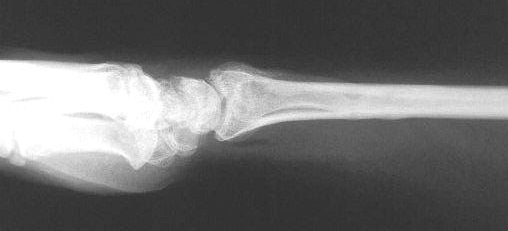

Clinical Example: Distraction plate fixation of distal radius fracture

A tricky case, for the patient previously had a large skin graft over the dorsal metacarpus / wrist / forearm. Incisions are marked here just before the plate was removed.

distal radius fracture

distraction plate